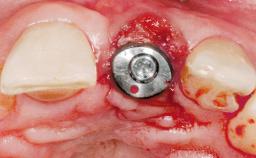

Late Placement of an Implant in a Maxillary Left Central Incisor Site

A 30-year-old female patient had lost tooth 21 and was referred to our clinic for consultation and treatment. Due to advanced apical infection, tooth 21 had been extracted two months earlier at another clinic and an acrylic-resin tooth had been bonded to the adjacent teeth. The patient desired implant treatment to avoid any damage to the adjacent natural teeth. While the patient had no history of any systemic disorder, she was a heavy smoker and exhibited medium to advanced periodontitis in the entire jaw. After the initial treatment to achieve a pocket probing depth of less than 4 mm and no bleeding on probing, a decrease in the height of the papillae mesial and distal to the extraction site and overall gingival recession were observed.

Bone Augmentation Horizontal|Staged

Augmentation Materials Autogenous chips|Membrane

Soft Tissue Grafting Simultaneous

Bone Volume Deficient horizontally, requiring prior grafting